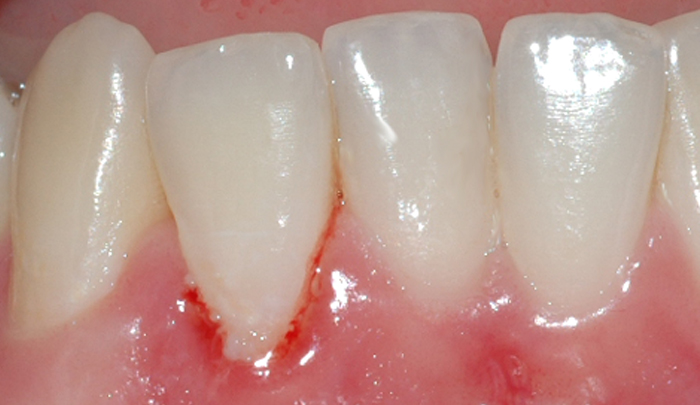

Fig 1: Et friskt tannkjøtt har lys rød farge og ligger stramt inntil tennene Fig 2: Mangelfullt renhold kan over tid føre til utvikling av gingivitt

Mangelfullt renhold kan over tid føre til utvikling av gingivitt. Dette skyldes bakterier og mykt belegg (plakk) som blir liggende på tannen i kontakt med tannkjøttet (fig. II). Om man har mye tannstein, vil også dette kunne medvirke til utvikling av gingivitt. Gingivitt oppstår lettest mellom tennene og ellers der det er vanskelig å holde rent.